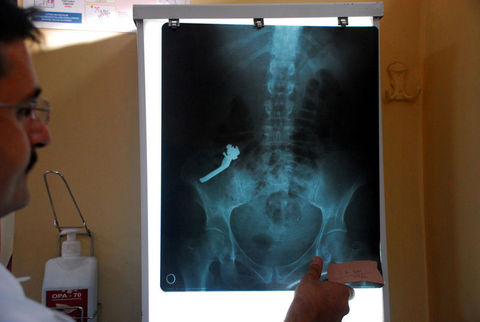

Van'da mide ağrısı şikayetiyle hastaneye kaldırılan kadının bağırsağından, 10 santimetre uzunluğunda vana kolu çıktı.

Alınan bilgiye göre, evindeki 10 santimetre uzunluğundaki metal vana kolunu yutan F.G, bir gün sonra şiddetli mide ağrısı şikayetiyle İpek Yolu Devlet Hastanesine kaldırıldı.

Yapılan tetkiklerde F.G'nin midesinde 10 santimetre uzunluğunda metal bir cismin bulunduğu görüldü. Doktorlar, vana kolu olduğu belirlenen cismin doğal yollarla vücuttan atılmasını bekledi.

Ancak midenin ardından kalın bağırsağa yerleşen cismin doğal yollardan vücuttan atılmayacağını tespit eden doktorlar, hastaya operasyon yapılmasına karar verdi. Yaklaşık 40 dakika süren operasyonda vana kolu bağırsaktan çıkarıldı.